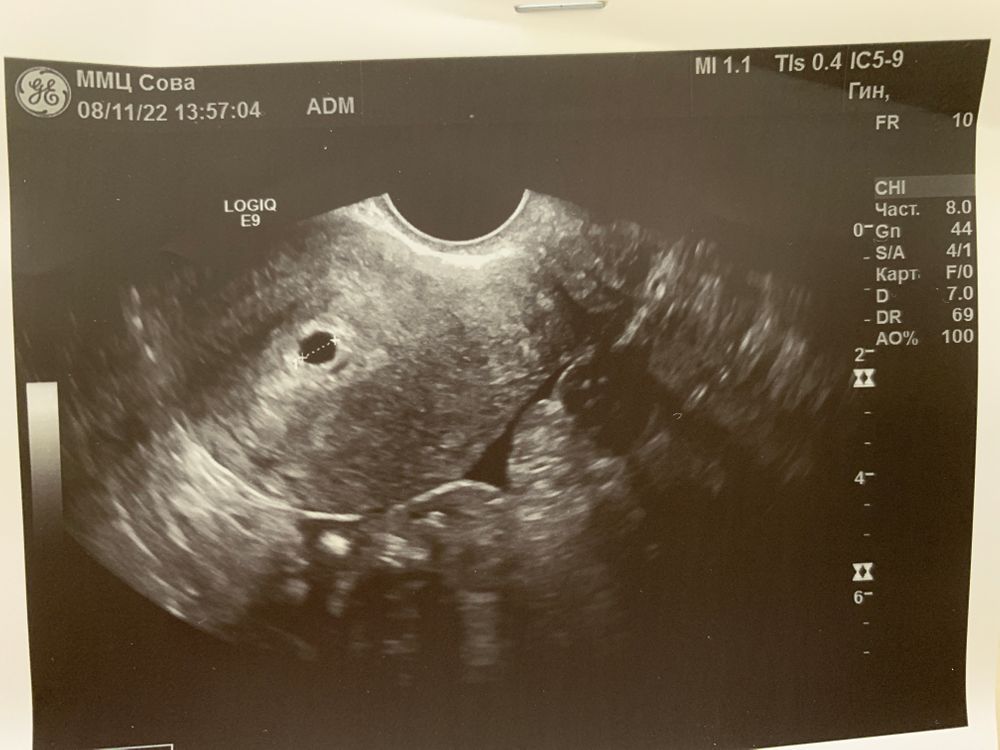

31дпп узи энд 10мм, ПЯ 3,5мм 👀👀👀, фоликул 19мм

38дпп узи ПЯ 5,5 мм,э и жм не видно

?? это остаток ПЯ? может он быть правильной ыормы и давать рост хгч 700-700?или это новая беременность при сбое гормонов?могут при новой беременности расти новые фоликулы в яичнике?

По мне так это либо остатки, либо тоже аномальная Б. и рост хгч не очень; и рост ПЯ. И что значит: выход хориальной ткани?на таких сроках ничего не возможно рассмотреть 🧐 если рассматривать ЕБ то по срокам 14 дней может и правда чудеса в горшочке, но тоже ни рост ни хгч не внушает доверия. Переделать узи, не затягивайте. Удачи 🍀

ТыКатя

Если учесть, что плодное не выросло почти с 31 по 38 дпп, то хорошего ждать не приходится к сожалению. Скорее всего остатки от переноса. Плодное растет по типу анэмбрионии и хгч нарастает плохо. В любом случае УЗИ еще в динамике для ответа на все вопросы. Хорошо, что не внематочная.